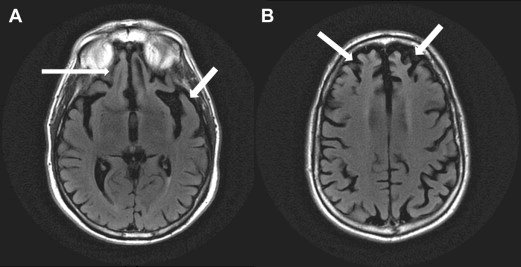

Il modello sperimentale, coordinato dalla ricercatrice del Center for Life Nano- & Neuro-Science, Silvia Di Angelantonio, affiancata da Paola Bezzi, ha sfruttato diverse cellule di pazienti con mutazioni della proteina tau per creare organoidi cerebrali, strutture tridimensionali di cellule nervose coltivate in laboratorio, che riproducono alcune caratteristiche tipiche della malattia. Si tratta della perdita di connessioni tra neuroni, di una ridotta attività funzionale e dell'accumulo di proteina tau patologica. Il trattamento con bezafibrato ha favorito l'aumento delle connessioni tra neuroni, recuperando parzialmente l’attività funzionale e riducendo l’accumulo di tau patologica, uno dei principali fattori della neurodegenerazione.